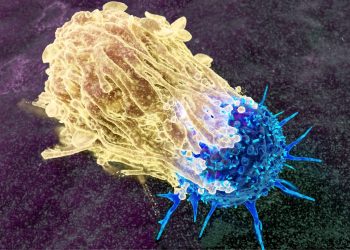

Εμβόλιο mRNA κατά του καρκίνου σε συνδυασμό με ανοσοθεραπεία μειώνει σημαντικά την υποτροπή του μελανώματος

Μια σημαντική επιστημονική εξέλιξη φέρνει νέες ελπίδες στη μάχη κατά του μελανώματος, της πιο θανατηφόρας μορφής καρκίνου του δέρματος. Σύμφωνα ...